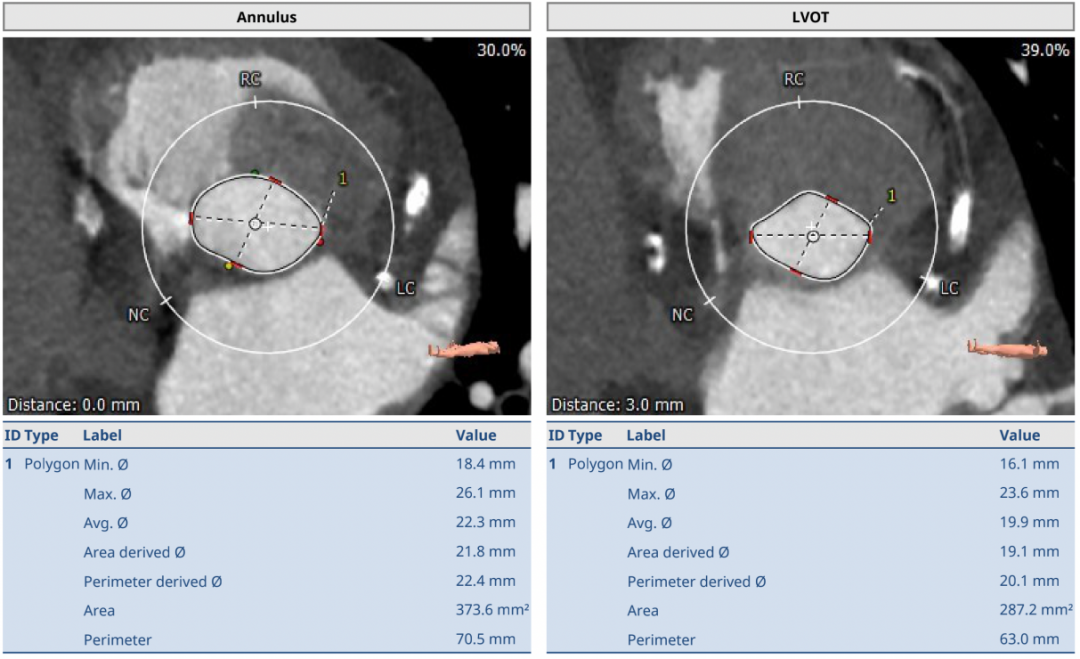

近日,武汉大学人民医院江洪教授团队成功挑战主动脉瓣严重狭窄合并钙化病变,顺利完成SAPIEN 3球囊扩张式瓣膜植入。在团队成员紧密配合下,克服患者弥漫钙化病变,顺畅完成过弓、跨瓣及释放操作,实现了手术的圆满成功。这是武汉大学人民医院首例应用SAPIEN 3瓣膜完成的TAVR。 患者基本情况 患者女性,78岁,既往有劳累性心绞痛,三支血管病变,右冠、前降支均存在大量钙化及狭窄,主动脉瓣严重狭窄伴中度钙化。 影像学检查结果 术前CT结果显示,主动脉瓣口面积373.6mm²,瓣环平均直径22.3mm,瓣环周长70.5mm;LVOT面积287.2 mm²,LVOT平均直径19.9mm;心夹角55°;左冠开口高度14.8mm、右冠开口高度16.2mm。 术前CT检查结果 手术策略讨论: